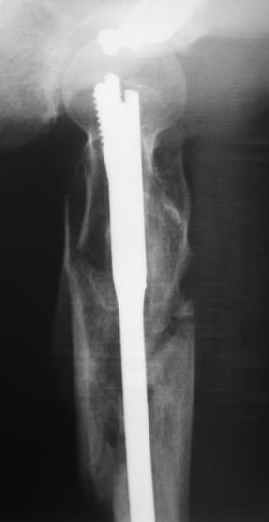

Наверно, можно и так сказать, но можно и тоже самое - 4-фрагментный вертельный перелом. Выбор тот же, но с учетом молодого возраста реконструкционный гвоздь тут более применим. Вот уже наш пример.

Перелом подвертельный. Лечение оперативное, срочное,

PFN с длинной ножкой чтобы избежать стрессовые изменения в будущем. Обычно у молодых людей требуется проводить рассверливание канала как при гвоздевании.

полную нагрузку через 6 недель т.е. после образования костной мозоли, что позволить более или менее сохранить длину шейки.